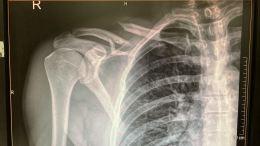

Klíčni kost

milanfiala

31